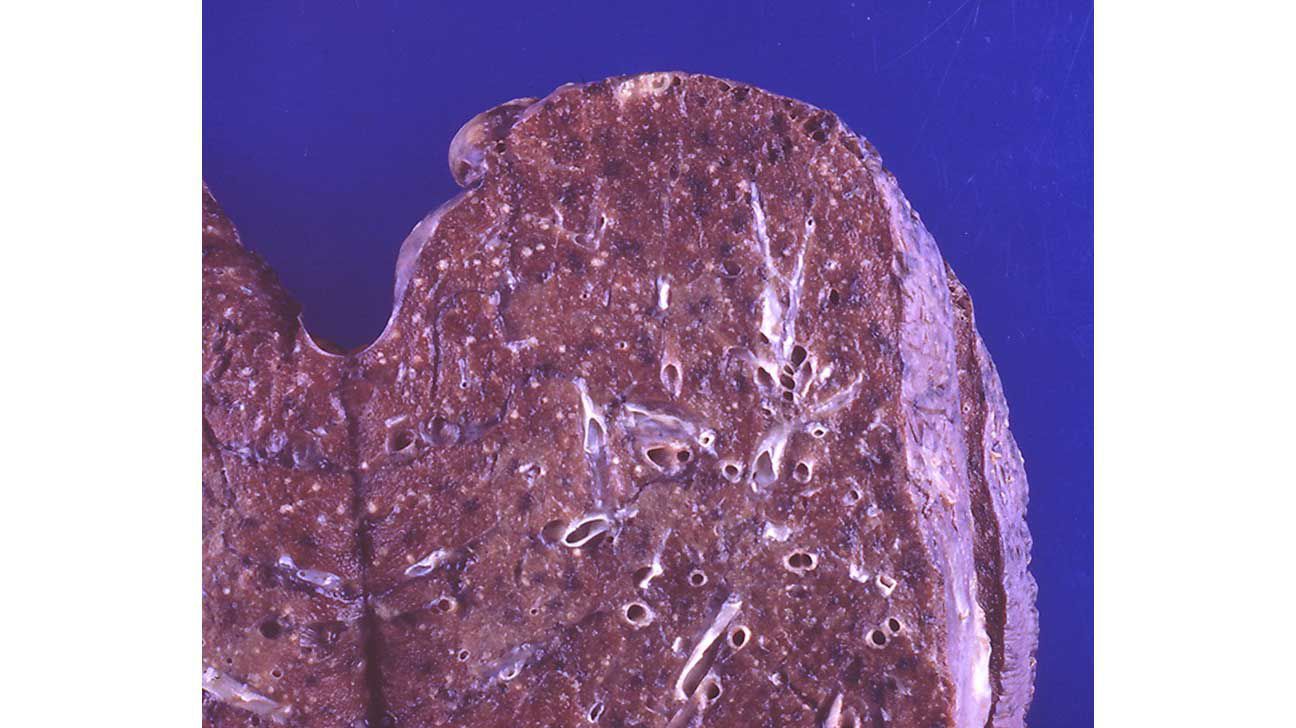

Miliary Tuberculosis

Miliary tuberculosis is a potentially life-threatening type of tuberculosis that occurs when a large number of the bacteria travel through the bloodstream and spread throughout the body. Tuberculosis. It usually affects the lungs.